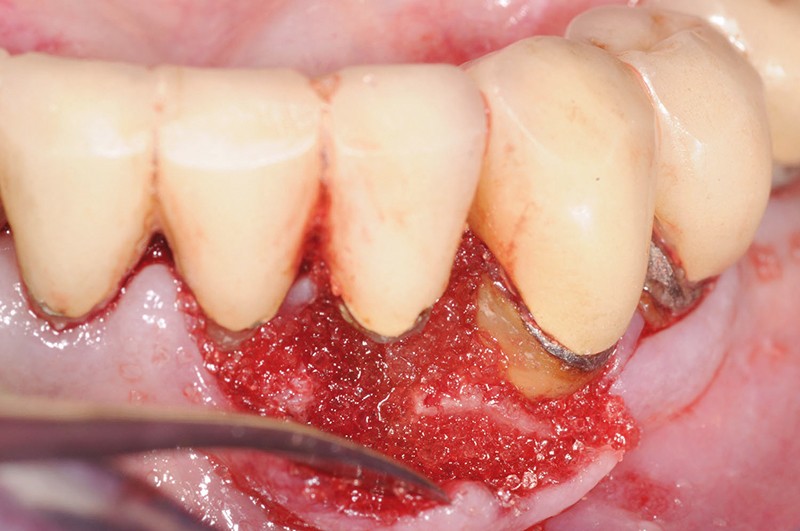

Le suivi à 6 ans de ce cas confirme donc les résultats prometteurs observés à court terme ainsi que les premières publications cliniques et fondamentales [4, 9]. Dans les chirurgies de préservation de crête, NovaBone® apparaît être un substitut fiable puisqu’à la réouverture à 4 mois, on note une reconstitution quasi ad integrum du volume osseux. De plus, le remplacement quasi complet des particules de NovaBone® par un os néoformé bien vascularisé permet la pose et le blocage des implants dans les sites [7].